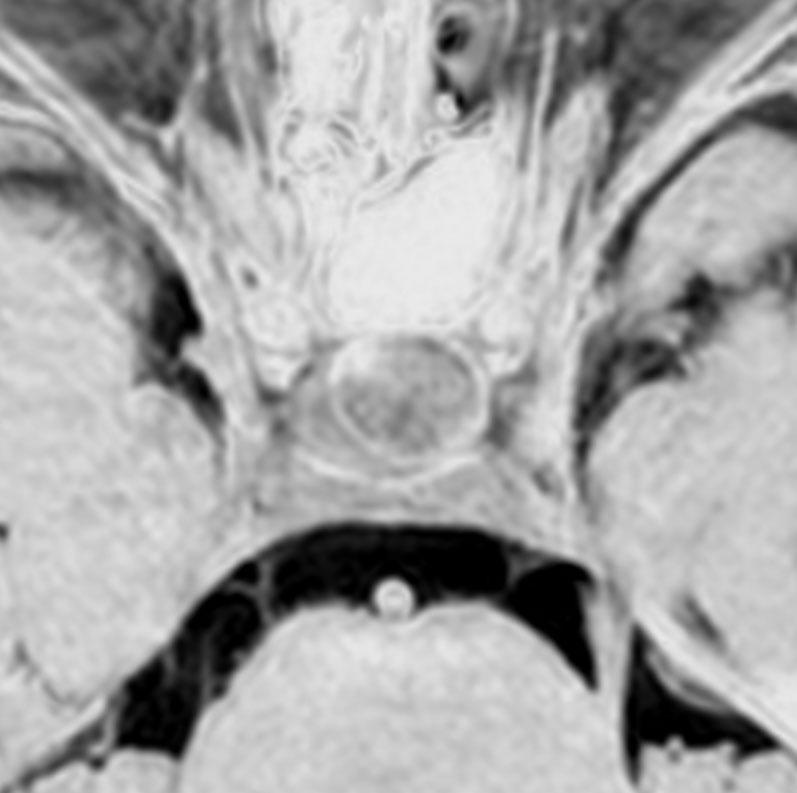

左と中央の画像でinfundibular recessの管腔が見え,左の視交差から視索の変形が強いことが解ります。右の画像では下垂体組織がトルコ鞍の右側に偏在してあります。画像では正常化錐体と明瞭な境界があるように見えるのですが,実際の手術所見では正常下垂体との境界は不鮮明でした。腫瘍のう胞からは黒褐色の内容液 machinery oil とコレステリン結晶が流出しました。厚いのう胞壁は硬膜と下垂体に強く付着して剥離するのが困難で切断して摘出しました。ラトケのう胞とはのう胞壁の厚さが異なると言えます。

術後5ヶ月のMRIです,無理して全摘出しませんでしたので残存腫瘍のように見えます。病理診断では,出血,慢性炎症性細胞浸潤を伴い,コレステリン結晶やヘモジデリンの沈着,泡沫組織球,多核巨細胞浸潤を伴った繊維性組織片に,少量の上皮組織塊があり,少量の正常下垂体組織も付着していると報告されました。施設によってはこの所見をラトケのう胞と病理診断するかもしれません。

術後には軽度の尿崩症がでましたが,1年半でデスモプレッシンを中断できて,下垂体機能は正常化しました。

1年半を要して残存腫瘍は徐々に縮小しました。この画像は術後3年半のもので,正常下垂体がトルコ鞍右側に偏って見えます。